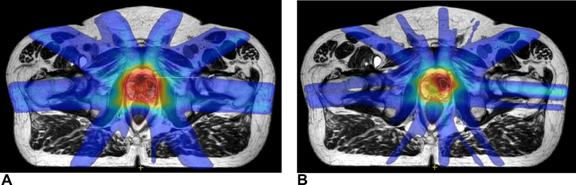

A sztereotaxiás kezelések dinamikusak, gyorsak és könnyedén kivitelezhetőek a Versa HD (High-Definition Dynamic Radiosurgery — Nagyfelbontású dinamikus sugársebészet) készülékkel. Preciz és gyors besugárzást biztosít, szabványos 15 perces időintervallumban teszi lehetővé az SBRT/SRS-kezelések elvégzését.

- Prosztata esetében a valós idejű lágyrész-követéssel történő kezelés az IntelliBeam segítségével kevesebb mint 90 másodperc alatt kivitelezhető.